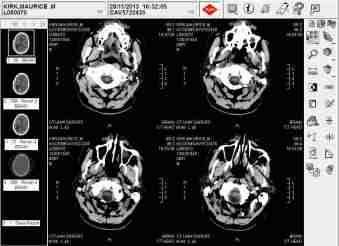

Then, without even appropriate medical qualifications concerning my specific brain scans taken on 28th September 2017, this very same NHS police doctor, who had me sectioned in August 2009 before His Honour Judge Llewellyn Jones QC without the need to even to attend court, further attempted to have me sectioned, on 2nd December 2009, for an indefinite term in custody simply because I had refused to use a free local lawyer that would, of course, of carried all its inherent dangers within any Cardiff court of law by adversely affecting my defence.

Your very own local authorities had gone on to falsely inform the English, US and French authorities, causing no less than ten unnecessary terms of my incarceration, in their misguided believe that I suffered from a possible ‘brain tumour’ causing irreversible but ‘significant brain damage’ which would most likely get worse if I persisted in pursuing my civil claims due to your successive Chief Constables’ bullying.

HMP Swansea Brian Scan

Concocted by Chief Constable Barbara Wilding and Adrian Oliver to having me ‘lawfully’ shot